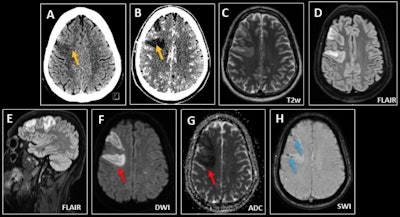

Septic emboli in a 40-year-old man with headache and acute confusional state in the context of bacterial endocarditis. (A-B) CT demonstrates a focal area of right frontal cortical edema, more evident in the postcontrast phase (yellow arrows), compatible with a subacute infarct or low-grade neoplasia. (C-G) MRI shows multiple scattered foci of increased intensity on T2/FLAIR, with restricted diffusion in both cerebral hemispheres, suggesting embolic infarcts (red arrows). (H) Dominant right frontal lesions associate microhemorrhage on susceptibility-weighted imaging (blue arrows).